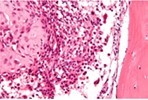

Upon microscopy, tumefaction is significantly cellular and composed of sheets of spherical to polyhedral chondroblastic cells imbued with abundant, eosinophilic cytoplasm and well demarcated cellular perimeter. Intracytoplasmic glycogen granules are evident. Nuclei appear elliptical, hyper-lobulated and demonstrate nuclear grooves. Nuclear atypia appears insignificant 1, 2.

Focal aggregates of spindle-shaped cells may be enunciated. Peri-cellular zones of ‘lace-like’ or ‘chicken wire’ calcification appear intermingled with degenerative chondroblasts. Eosinophilic foci of chondroid matrix are invariably discerned 1, 2.

Focal mitotic activity, necrosis and osteoclast-like giant cells may be commingled with cellular zones. Besides, aneurysmal bone cyst-like modifications are commonly observed 1, 2.

Figure 2.Chondroblastoma delineating aggregates of polyhedral chondroblastic cells with angulated, abundant, eosinophilic cytoplasm and vesicular nuclei enmeshed within a chondomyxomatous matrix6.